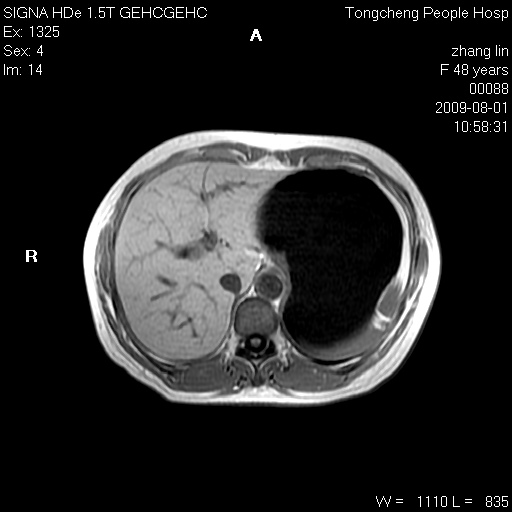

女,48岁。健康体检,彩超发现右肾占位性病变。平素健康。

临床诊断:右肾占位性病变,性质待定(囊肿?肿瘤?)。

上中腹部mr平扫+增强扫描,图像如下:

右肾上极见一类圆形病灶,t1wi呈等信号t2wi呈等高混杂信号,三期增强无强化,边界清---考虑囊肿出血。

慢性胆囊炎